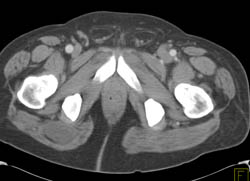

Dislocation of Hip in 3D With Disarticulation